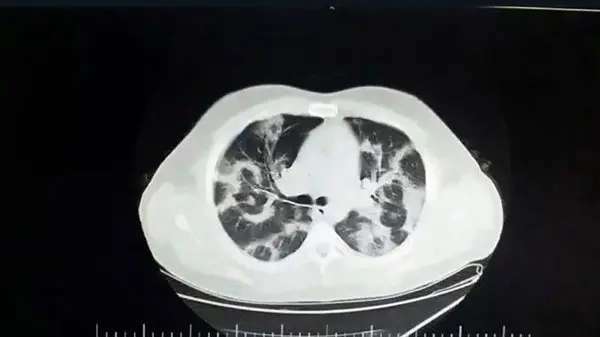

اولین عکس از ریه کرونایی انگلیسی / هشدار برای زیر 20 ساله ها!

کرونای انگلیسی جهش یافته افراد سن پایین را درگیر می کند و در سی تی اسکن بیماران جوان مبتلا به کرونای انگلیسی ریه های بلافاصله درگیر می شود و بعد از 3 روز فرد دچار علامت خواهد شد.